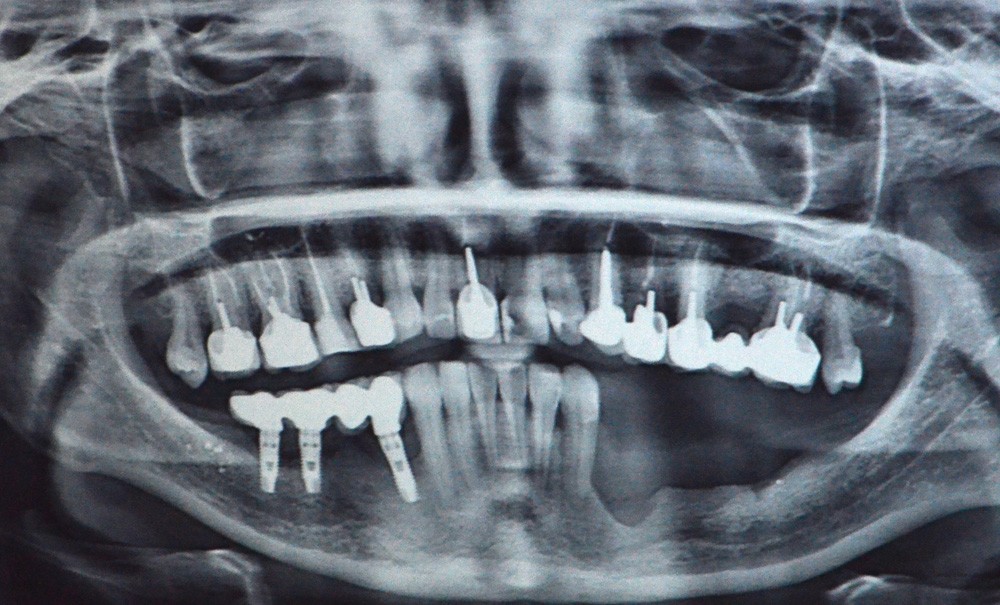

Il s’agit d’une jeune patiente 38 ans ayant présenté une perte osseuse à la suite de péri-implantite. Les implants ont été déposés. La patiente présente une atrophie mandibulaire postérieure classée Cawood V (fig. 1).